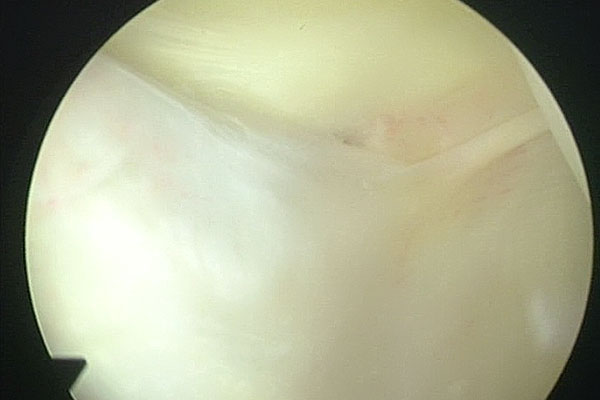

Arthroscopic Management of Baker's CYST